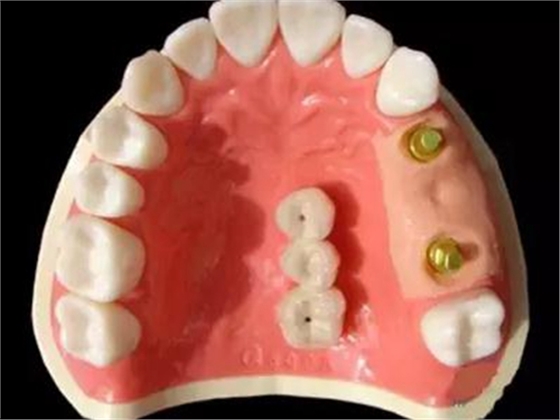

種植支持式固定義齒外展隙面積影響食物嵌塞

8月13日在線發(fā)表于《牙周病學雜志》(J Periodont)的一項橫斷面研究顯示,種植支持式固定義齒和鄰牙間的食物嵌塞更易發(fā)生于鄰接觸喪失及外展隙表面積(ESA)增加的情況下。食物嵌塞降低了患者的總體滿意度。外展隙尺寸影響牙周/種植體周黏膜的狀態(tài)及種植體的骨水平。

本研究納入了100例患者(55 例男性,45 例女性),平均年齡56歲(27~83歲),共150個固定義齒的215個外展隙。牙周/種植體周圍黏膜狀態(tài)、外展隙尺寸及患者總體滿意度作為解釋變量。

結果在種植支持式固定義齒和鄰牙間的215個外展隙中,96個(44.7%)有食物嵌塞。鄰接觸喪失外展隙較緊密接觸者更易發(fā)生食物嵌塞(P=0.009)。鄰面外展隙的食物嵌塞降低了總體滿意度(P=0.012)。在外展隙參數中,僅ESA明顯影響食物嵌塞(P=0.034)。不同的外展隙尺寸對牙周/種植體周黏膜狀態(tài)和種植體骨水平有顯著影響。